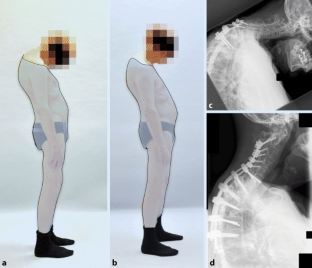

Abb. 1